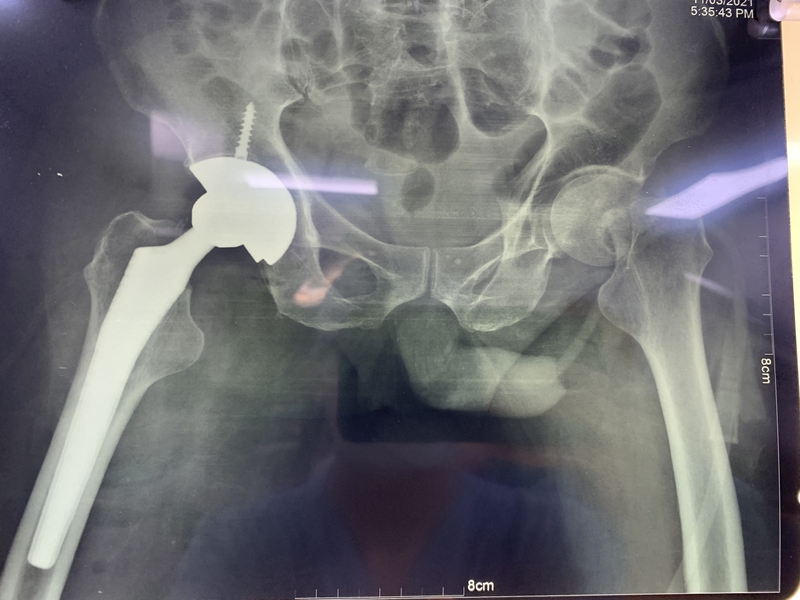

Phẫu thuật thay khớp háng là một quá trình phẫu thuật nơi khớp bị hỏng được thay thế bằng một khớp nhân tạo, giúp giảm đau và phục hồi nhanh chóng khả năng hoạt động hàng ngày. Thay khớp háng thường được chỉ định trong các trường hợp của bệnh thoái hoá, hoại tử chỏm vô khuẩn và chấn thương. Đây là một phẫu thuật phức tạp và yêu cầu bác sĩ có kiến thức chuyên môn sâu, đồng thời phải tiến hành quá trình kiểm tra kỹ lưỡng và đánh giá tình trạng của bệnh nhân trước khi tiến hành phẫu thuật.

Vì vậy, những người cao tuổi bị gãy cổ xương đùi và có cả hai yếu tố như vậy thường chọn phương pháp thay khớp háng nhân tạo để khôi phục khả năng vận động và tránh các biến chứng có thể xảy ra do nằm lâu.

Thay khớp háng ở người già đã trở thành một giải pháp quan trọng trong việc cải thiện chất lượng cuộc sống và khôi phục khả năng vận động cho những người già bị gãy cổ xương đùi. Quá trình này không chỉ giúp giảm đau mà còn đóng vai trò quan trọng trong việc mang lại sự tự tin và độc lập cho người bệnh. Tuy nhiên, để phẫu thuật thay khớp háng bệnh nhân cần phải được tầm soát tốt, tiên lượng những nguy cơ biến chứng có thể xảy ra để đạt được kết quả tốt nhất.